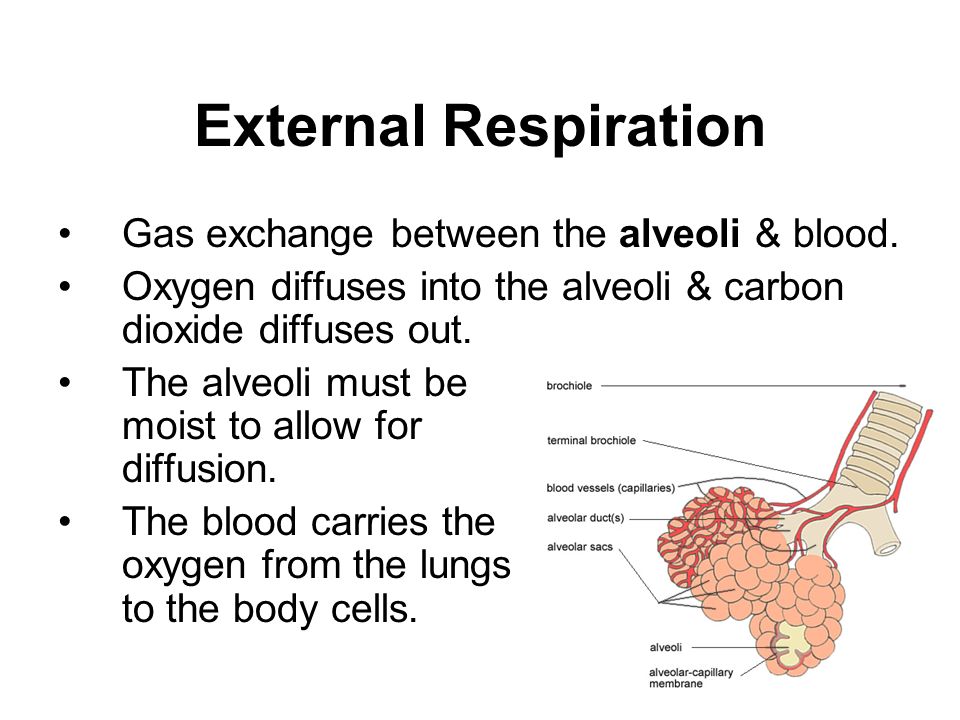

1. External Respiration:

This is breathing which involves exchange of gases and it takes place in the lungs. This simply involves the breathing of air or oxygen into the lungs. This is also called inspiration or inhalation and the breathing out of air (carbon dioxide and water vapour) into the atmosphere and environment is otherwise called expiration or exhalation.

2. Internal Respiration:

1. External Respiration:

This is breathing which involves exchange of gases and it takes place in the lungs. This simply involves the breathing of air or oxygen into the lungs. This is also called inspiration or inhalation and the breathing out of air (carbon dioxide and water vapour) into the atmosphere and environment is otherwise called expiration or exhalation.

2. Internal Respiration:

This involves the breaking down of food substances and release of energy. It takes place within the cells of the body.